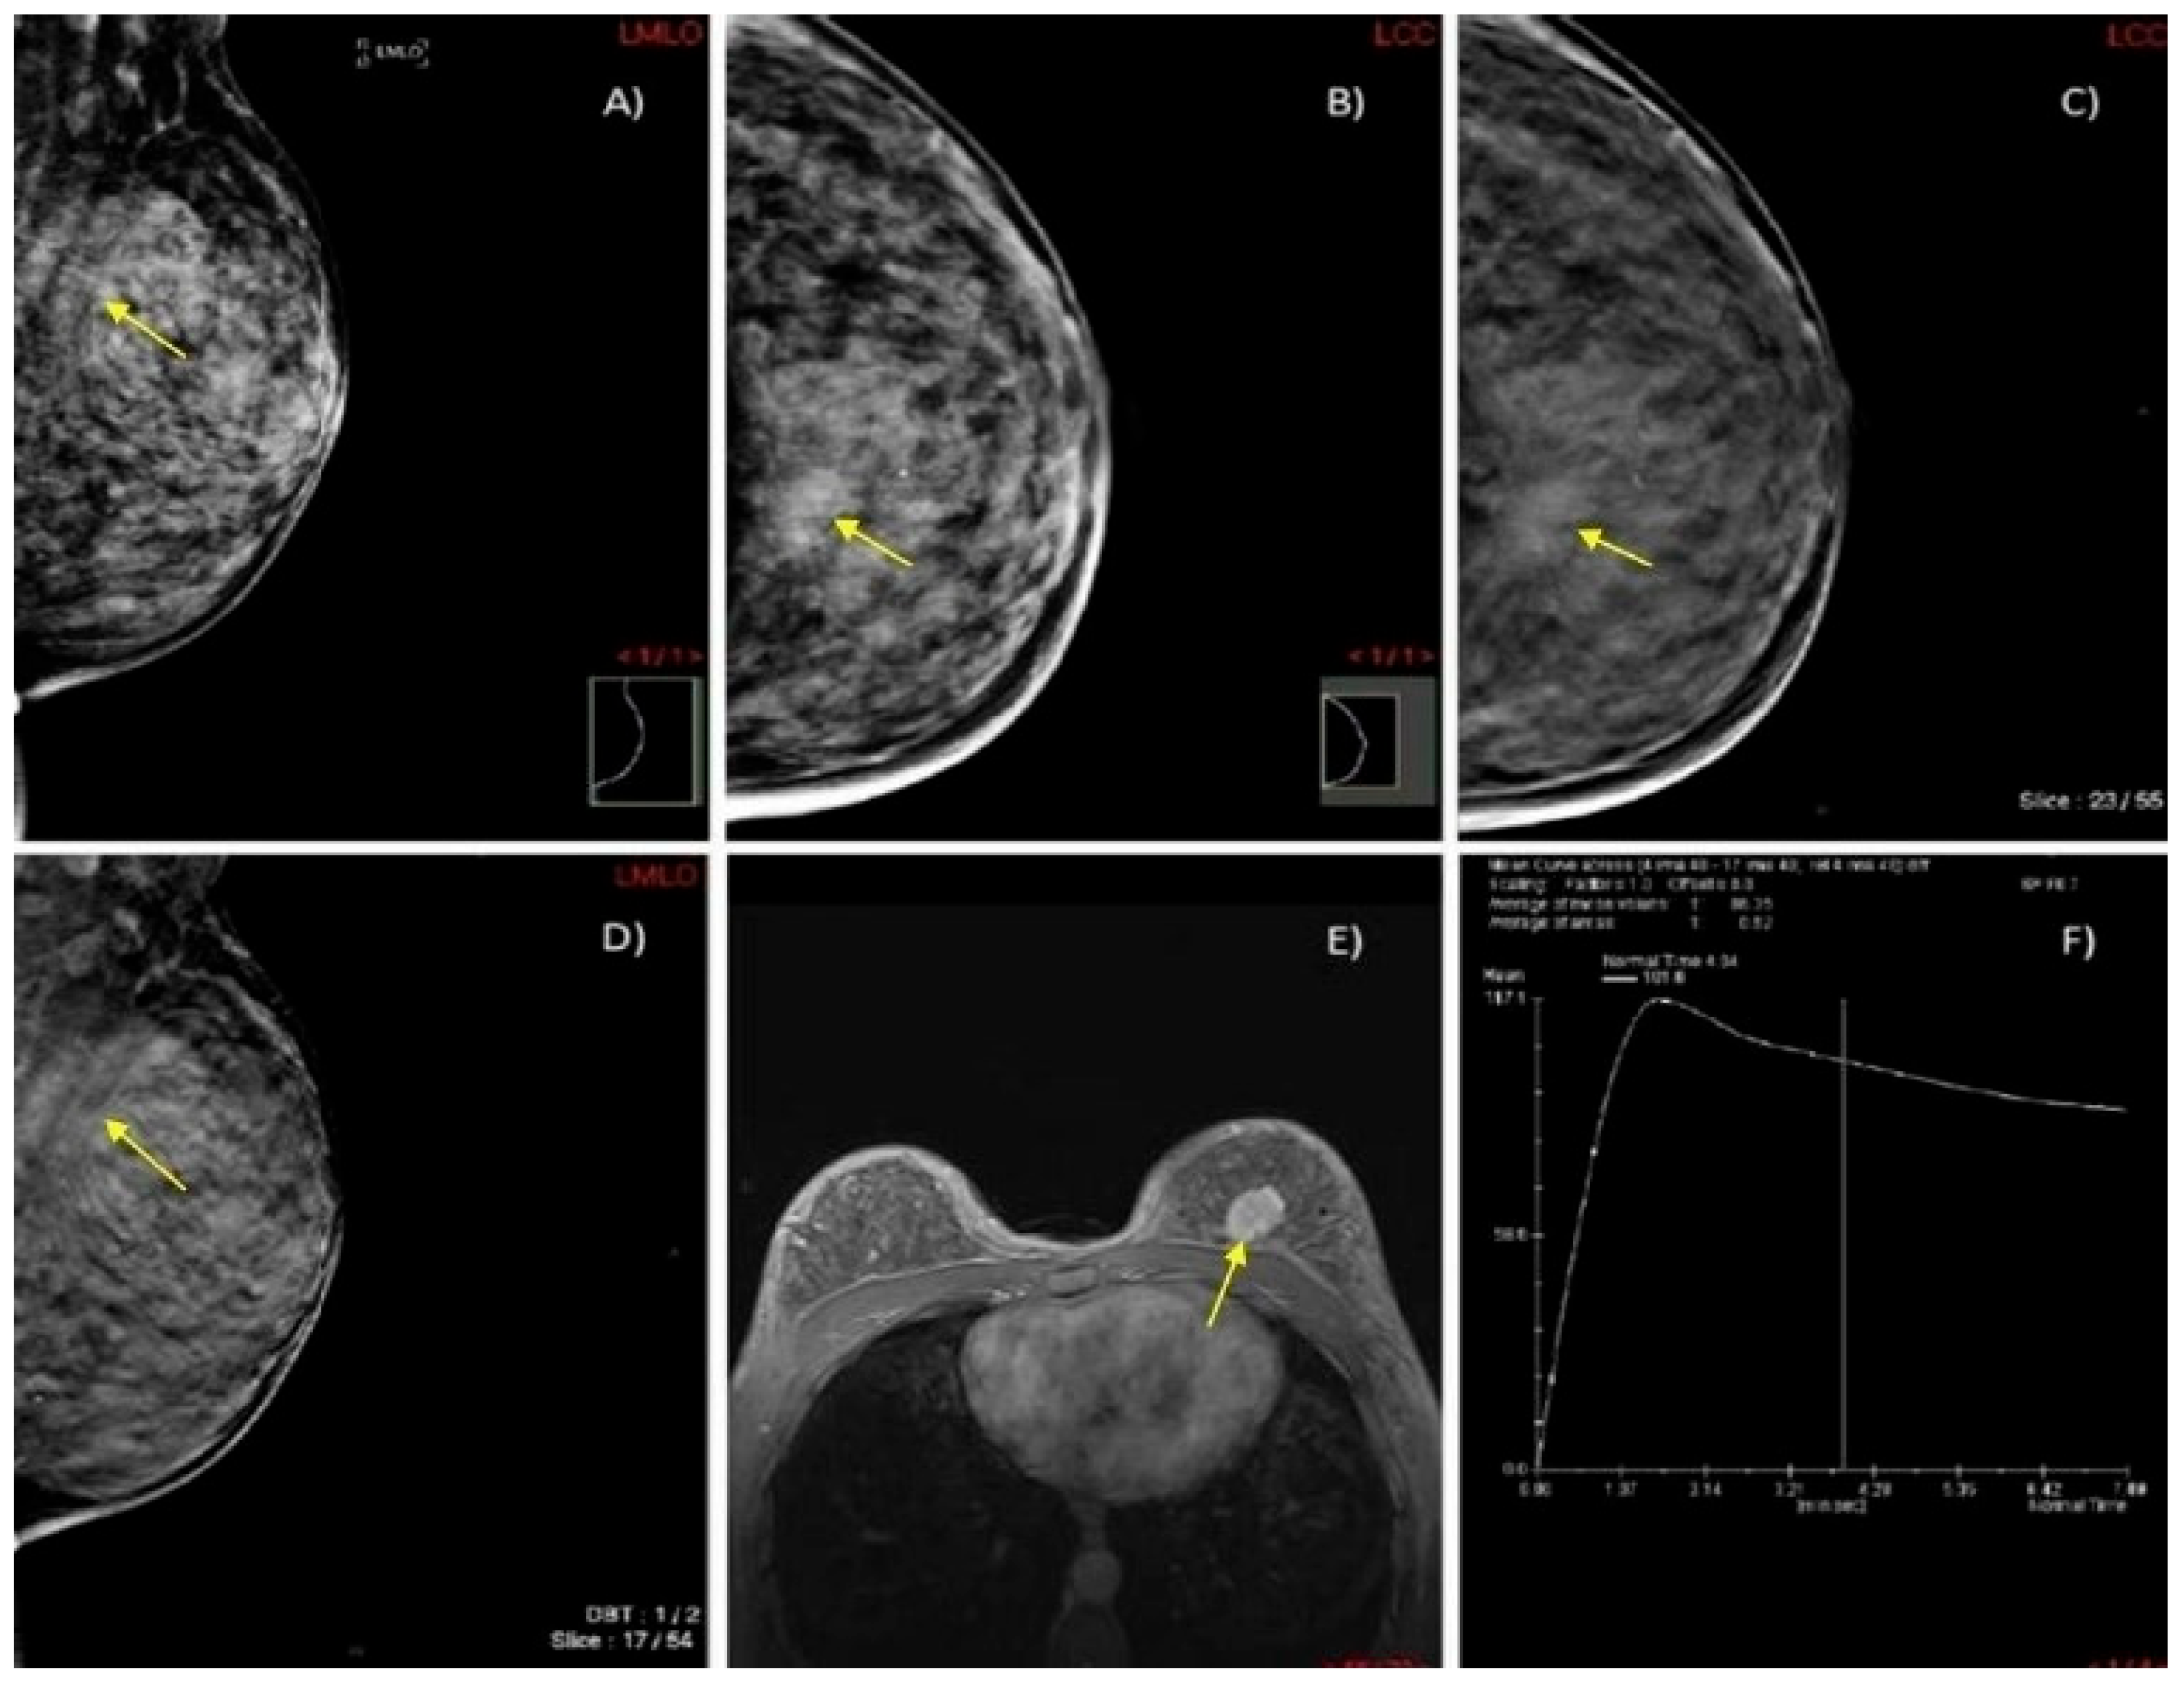

Diagnostic Imaging: Breast, 2nd Ed. ― Published by Amirsys。Breast Imaging 2 Fall 2025 | Canadian Association of Medical。Quantra® 2.2 | Breast Density Assessment Software | Hologic。マンモグラフィーや超音波などの診断技術を網羅した、拡大改訂版の医学書。Computer-aided detection enhances breast MRI | AuntMinnie。- 書籍名: Diagnostic Breast Imaging- 著者: Sylvia H. Hewayng-Köbrunner, D. David Dershaw, Ingrid Scherer- 版: 第2版, 拡大改訂版- 出版社: Thieme- 内容: マンモグラフィー、超音波、磁気共鳴画像、介入手技に関する情報ご覧いただきありがとうございます。。